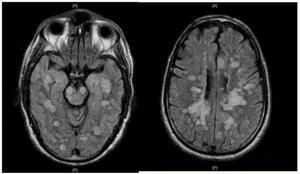

| Fulminating ADEM showing many lesions. The patient survived, but remained in a persistent vegetative state | |

ADEM produces multiple inflammatory lesions in the brain and spinal cord, particularly in the white matter. Usually these are found in the subcortical and central white matter and cortical gray-white junction of both cerebral hemispheres, cerebellum, brainstem, and spinal cord,[16] but periventricular white matter and gray matter of the cortex, thalami and basal ganglia may also be involved.